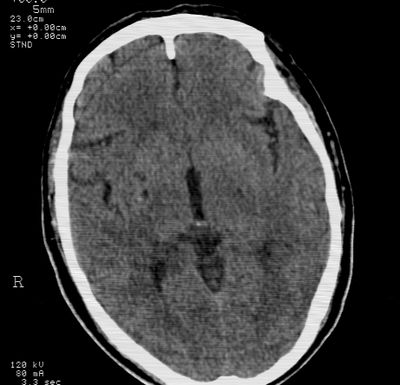

标题: CT21793:李x,男,62岁,头疼,头晕,家属否认有出血病史, [打印本页]

标题: CT21793:李x,男,62岁,头疼,头晕,家属否认有出血病史,

右枕叶.右侧脑室前角旁脑梗塞

右基底节,海马并侵及右枕,左枕叶梗塞

右枕叶.右侧脑室前角旁脑梗塞。

支持多发脑梗塞

支持右基底节,海马并侵及右枕,左枕叶梗塞。

支持右基底节,海马并侵及右枕,左枕叶梗塞。建议增强。

多发性梗塞

多发梗塞,左小脑软化灶

多发性脑梗塞。

考虑多发脑梗塞,建议mri检查。